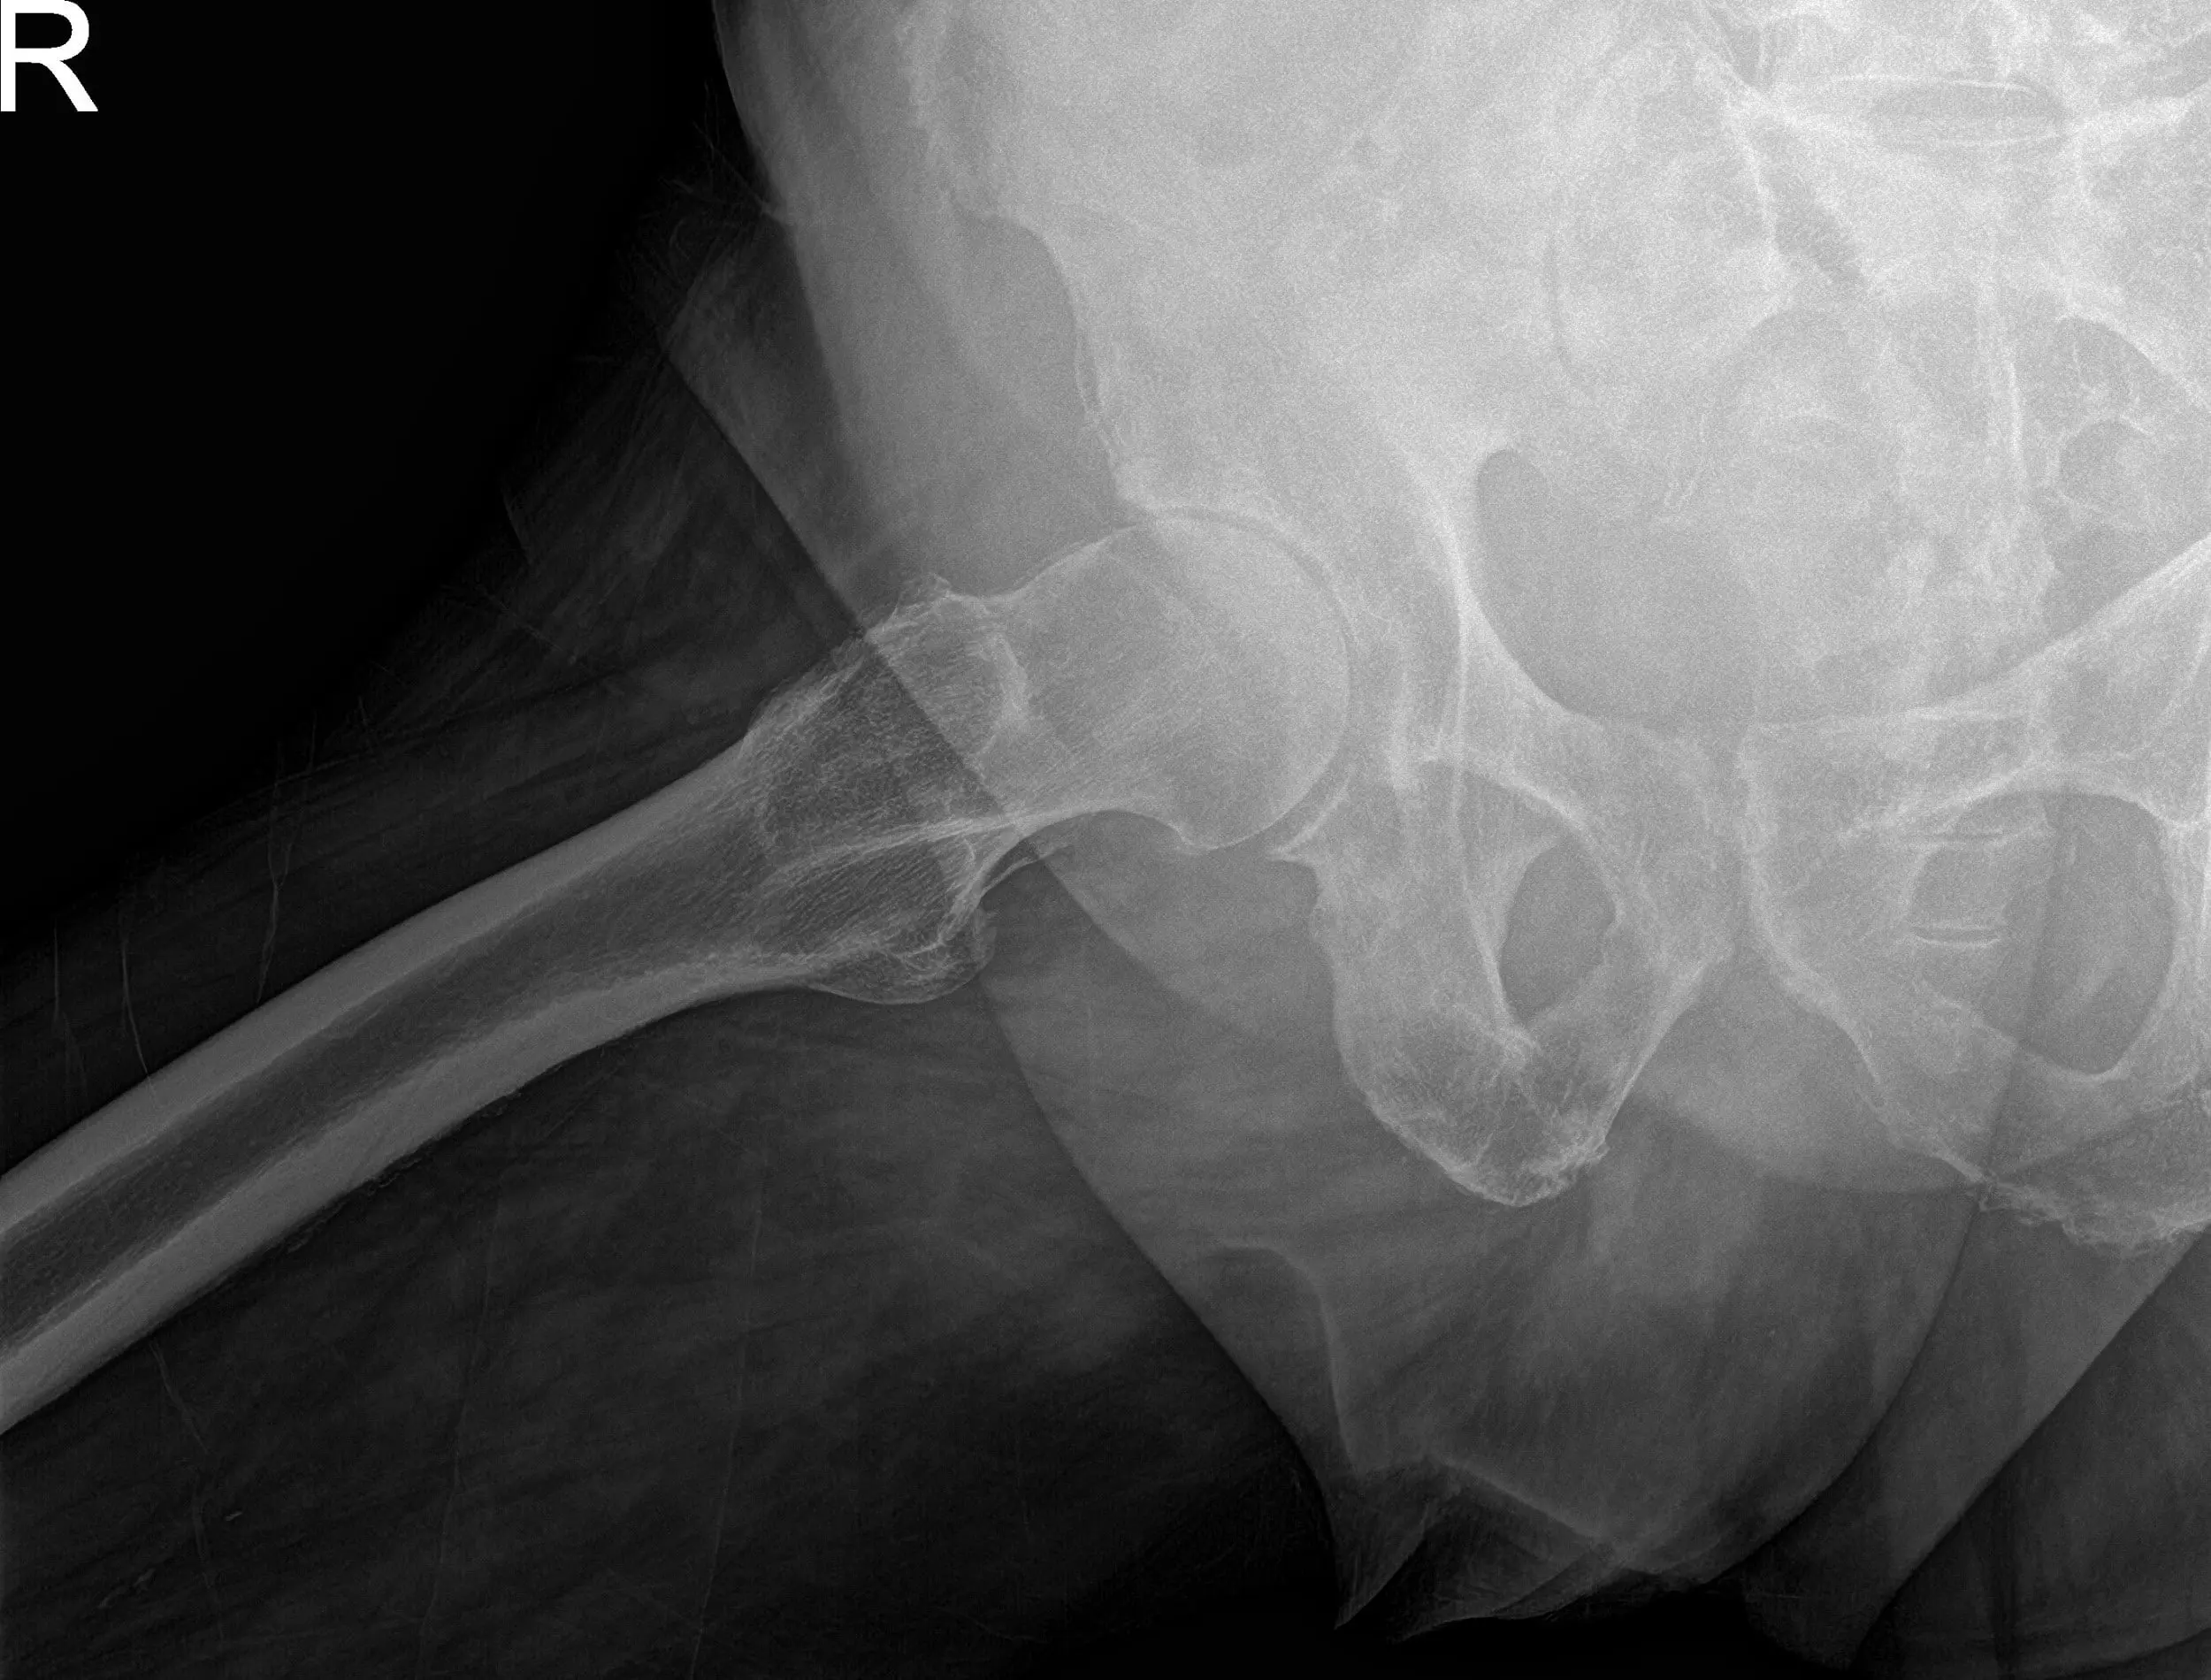

Postoperative X-ray showing AP and frog-leg lateral views of the right hip